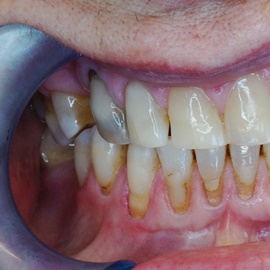

Wybielanie obejmujące pojedyncze zęby jest dość często spotykane. Najczęstszą przyczyną dyskoloracji zęba jest obumarcie miazgi i brak następowego poprawnego leczenia kanałowego, lub leczenie nieprawidłowe. Czasami udaje się przeprowadzić proces wybielania, który jest zadowalający dla pacjenta, a czasami w oparciu o uzyskany wynik można przeprowadzić leczenie protetyczne np. koroną lub licówką całoceramiczną.

Trzeba jednak uważać, ponieważ nieumiejętnie przeprowadzone wybielanie może być przyczyną resorpcji wewnętrznej i może sie skończyć utratą całego zęba...juz wybielonego. Poniżej zdjęcia przed i po leczeniu mikrochirurgicznym resorpcji.